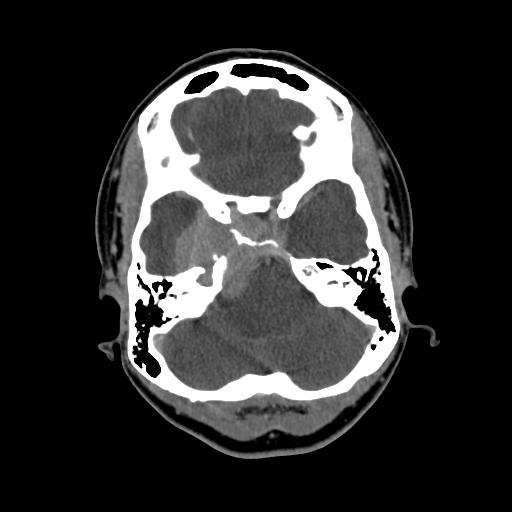

Infectious/Mycotic Aneurysm

Pre-contrast

Post Contrast